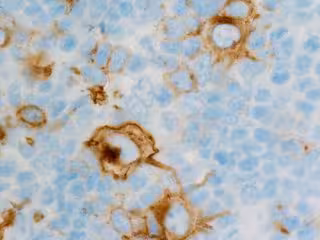

Linfoma de Hodking - FLIKR/CNICHOLSONPATH - Archivo

El linfoma difuso de células B grandes representa entre un 30 y un 40 por ciento de los linfomas no Hodgkin y, aunque puede aparecer en cualquier edad, suele afectar principalmente a pacientes de en torno a los 60 años. Son linfomas agresivos, en los que aproximadamente 1 de cada 3 pacientes no responde a las terapias convencionales, por lo que es fundamental avanzar en su conocimiento, para encontrar tratamientos más eficaces.